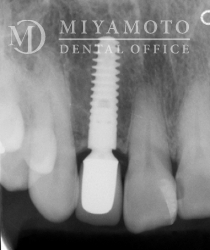

症例2

左上中切歯部インプラント

同部位エックス線